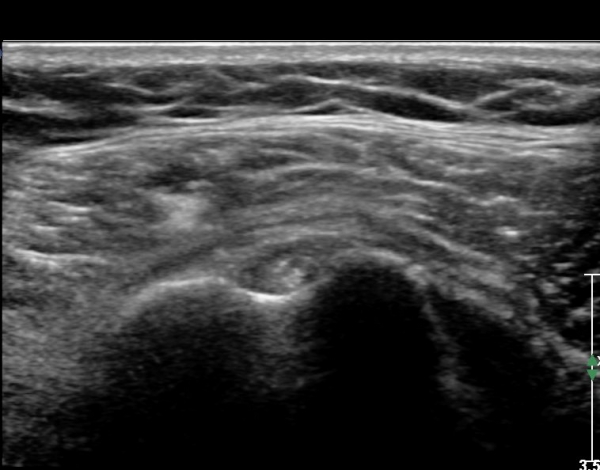

ÃÊÀ½ÆÄ ¼Ò°ß: ¿À±¸µ¹±â¿Í °ßºÀÀ» ¿¬°áÇÏ´Â ¿À±¸µ¹±â°ßº»Àδ밡 Á¤»óÀûÀÎ ¸ð½ÀÀ¸·Î °üÂûµÈ´Ù(»çÁø 1).

ŽÃËÀÚ¸¦ Á¶±Ý ¸»´ÜÀ¸·Î À̵¿ÇÏ´Ï ¿À±¸µ¹±â°ßºÀÀÎ´ë °ßºÀ ºÎÂøºÎ °ñ±ØÀÌ °üÂûµÇ°í ÀÎ´ë ½ÉÃþºÎ¿¡ ¼ö¾×Àú·ù°¡ ÀÖ¾î ¸¸¼ºÀûÀÎ Ãæµ¹À» ÃßÁ¤ÇÒ ¼ö ÀÖ´Ù(»çÁø 2).